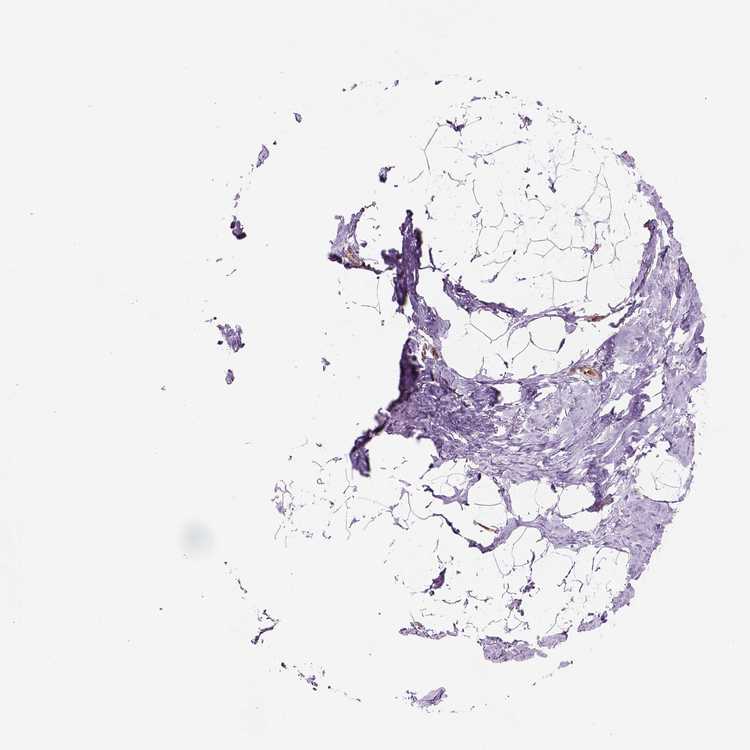

TISSUE PRIMARY DATA BREAST Show tissue menu

BREAST - Antibody stainingi

Antibody staining in the annotated cell types in the current human tissue is reported as not detected, low, medium, or high, based on conventional immunohistochemistry profiling in selected tissues. This score is based on the combination of the staining intensity and fraction of stained cells.

Each image is clickable and will lead to virtual microscopy that enables deeper exploration of all samples and also displays staining intensity scores, fraction scores and subcellular localization as well as patient and tissue information for each sample.

Antibody HPA042275Antibody HPA067433

Adipocytes Not detectedLow

Glandular cells Not detectedLow

Myoepithelial cells Not detectedLow